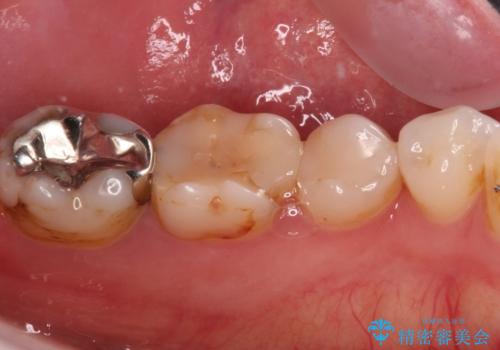

- 奥歯の詰め物や周辺の歯が欠けてしまったとのことで来院された患者様です。

上顎は、元々の詰め物が小さく、欠けた範囲も大きくなかったため、セラミックインレーにて修復治療を行うこととしました。

一方下顎は、元々のむし歯の範囲が広かったため、長期的な予後を踏まえ、セラミッククラウンにて補綴治療を行うこととしました。